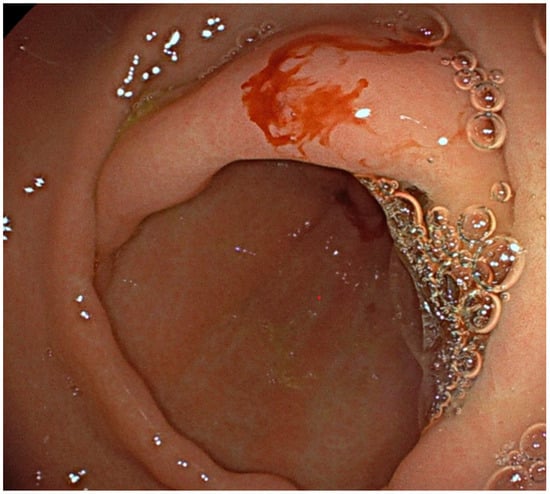

| Lower GI Bleeding (%) | 86 |

| Angiodysplasia (%) | 70.4 |

| Diverticular disease (%) | 7.7 |

| Inflammatory disease (%) | 5.4 |

| Hemorrhoids (%) | 3.1 |

| Upper GI Bleeding (%) | 9.4 |

| Liver failure, portal hypertension, esophageal varices | 6.2 |

| Gastroduedenal erosion | 3.2 |

| Obscure occult (%) | 4.6 |